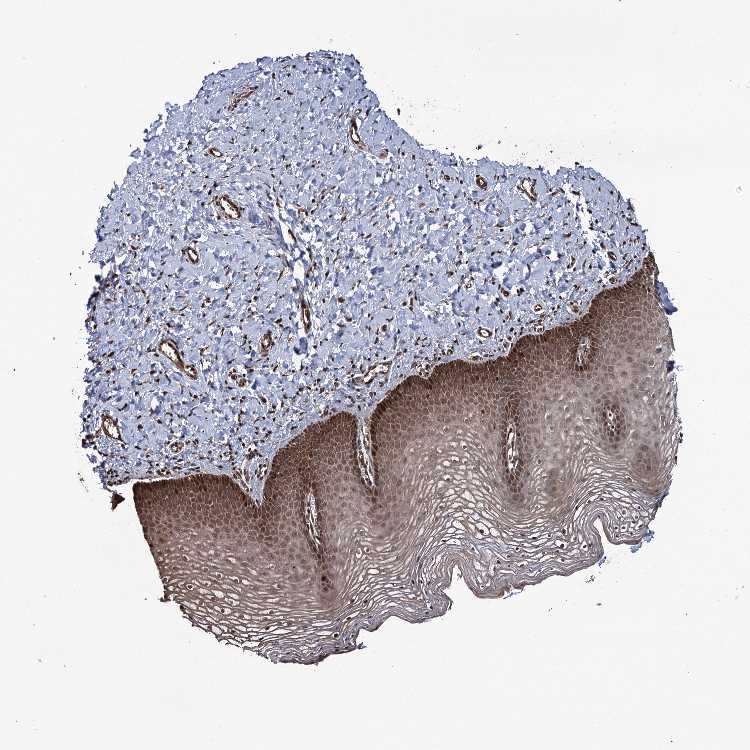

TISSUE PRIMARY DATA VAGINA Show tissue menu

VAGINA - Antibody stainingi

Antibody staining in the annotated cell types in the current human tissue is reported as not detected, low, medium, or high, based on conventional immunohistochemistry profiling in selected tissues. This score is based on the combination of the staining intensity and fraction of stained cells.

Each image is clickable and will lead to virtual microscopy that enables deeper exploration of all samples and also displays staining intensity scores, fraction scores and subcellular localization as well as patient and tissue information for each sample.

Antibody HPA004805Antibody HPA038771Antibody HPA038772

Squamous epithelial cells HighMediumMedium